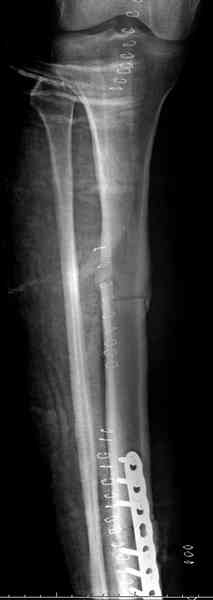

Недавно на нашей ежемесячной Morbidity&Mortality

conference мы разбирали похожий случай, ложный сустав большеберцовой кости после резекции опухоли.

К нашему онкологу-ортопеду обратился больной с жалобами на боли в голени, из рассказа - год назад была сделана биопсия большеберцовой кости, но название заболевания "не запомнил”.

Оперирован в военном госпитале с заменой сегмента

аллокостью большеберцовой кости и после демобилизации явился для постоянного наблюдения по месту жительства.

В литературе "A Classic Adamantinoma Arising from

Osteofibrous Displasialike Adamantinoma in the Lower Leg: A case report and Review of the Literature похожие снимки.

Наши имели проблему со сращением, пришлось им сделать динамизацию, дополнительную аутопластику.

Снимки представлены.